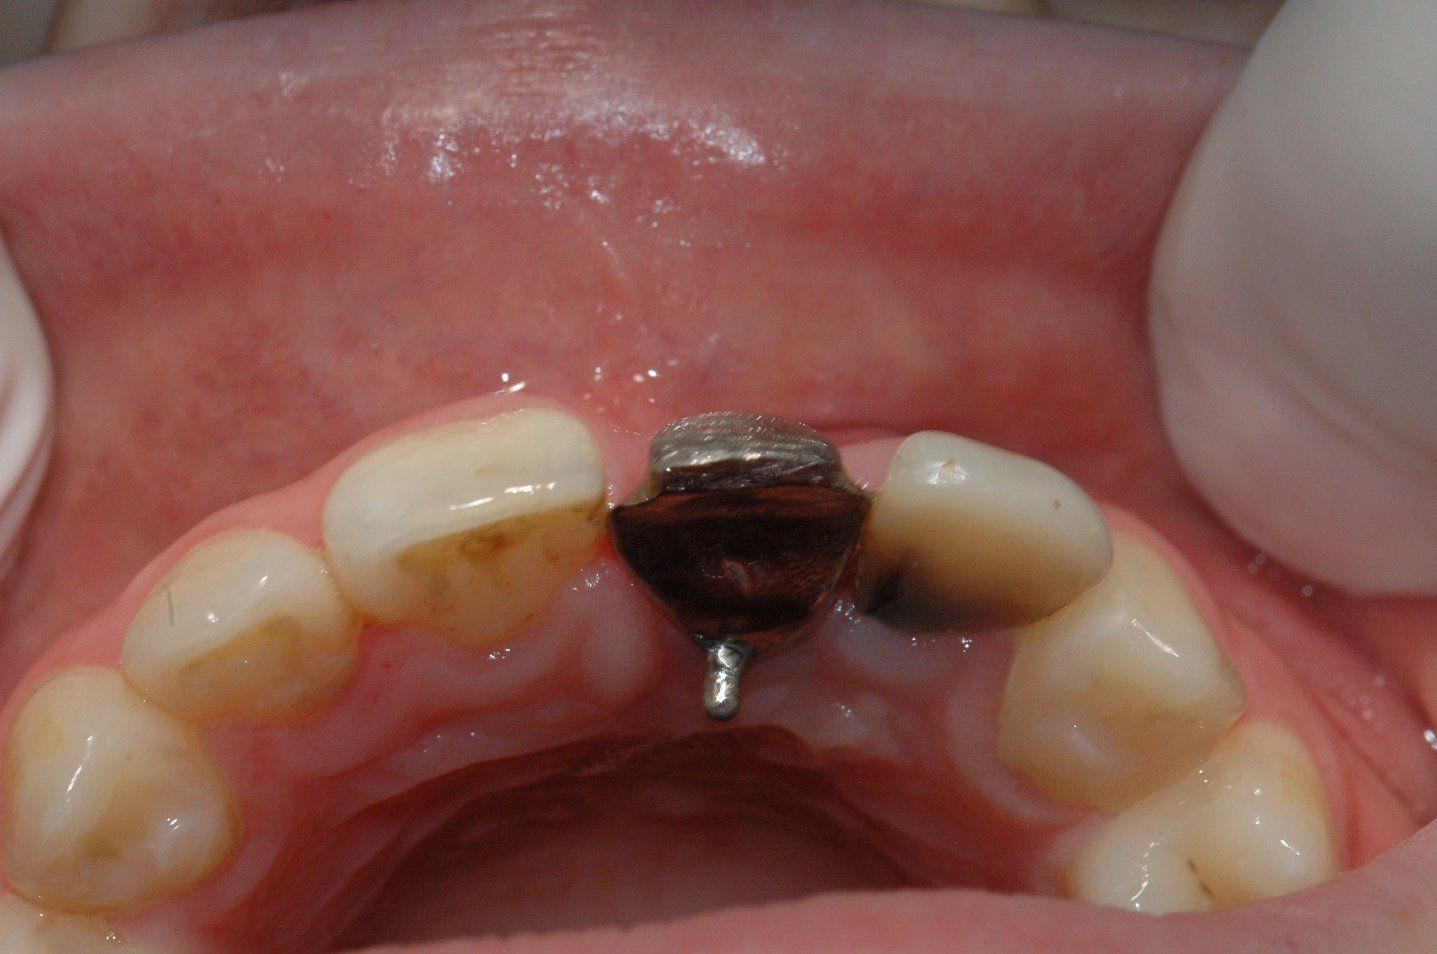

Nel 1994 una paziente di 28 anni subì la frattura dell’incisivo centrale superiore sinistro precedentemente trattato endodonticamente

Un caso analogo al precedente.

Una giovane signora di ventotto anni subisce nel 1996 la frattura dell’incisivo centrale superiore destro

in precedenza trattato endodonticamente